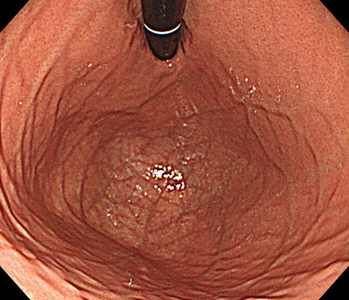

胃内視鏡(胃カメラ)画像

| ◆ 経口内視鏡(高解像度)◆ | ◆ 経鼻内視鏡 ◆ |

| 胃 | 胃(経鼻) |

※ 経鼻内視鏡はカメラの径が細いぶん、解像度が低く暗い画像となり病変の見逃しが多くなる傾向があります。